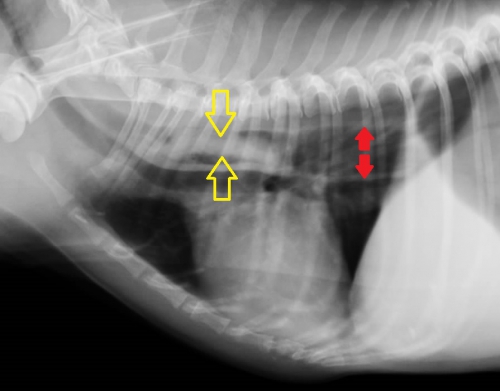

下写真は胸部レントゲン検査の画像です。【ケース1】と同様に黄色の矢印の間にわずかに白いエリアが見られます。

確定診断のための造影レントゲン写真は下のようになりました。バリウムの侵入が少なくやや見にくいですが、四辺形らしい形のはっきりしない食道内異物が確認できます。

【ケース1】の異物よりも造影剤が入らないため見えにくくなっていますが、これは異物が食道粘膜と密着しているということを意味します。その意味は内視鏡検査の際に明らかになります。

下の写真が胸部レントゲン写真です。黄色い矢印に挟まれた「白く細長い異物が見えると思います。この場所は胸部食道の心基底部(心臓の上)に近い部分で、食道閉塞を起こしやすい場所です。写真ではまた。食道閉塞に伴って飲み込んだ空気によって食道拡張がみられています。(右の赤い矢印の間)

ふつう、食道はレントゲン写真に写らないのですが、このわんちゃん、かなり苦しかったらしく大量の空気を飲んでおり、食道と胃に空気が入っています。このため、飲みこんだ空気が「造影剤」となって、異物が「空気造影」されており、幸いにもレントゲン写真で異物の存在が明らかになりました。

食道の状況を見るためにバリウム造影を行ったのが右下の写真です。造影剤は異物の周囲を速やかに通り抜けており、異物は食道に密着している状態ではない様子ですが、どうも両端で食道に引っかかっているような感じではないでしょうか。